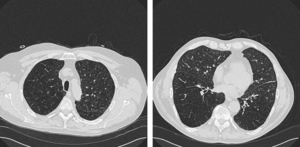

Publication: J Thorac Imaging. 2016 Jan;31(1):29-36. PMID: 26429588| PDF Authors: Zach JA, Williams A, Jou SS, Yagihashi K, Everett D, Hokanson JE, Stinson D, Lynch DA, COPDGene Investigators. Institution: Divisions of Radiology, Biostatistics and Bioinformatics, National Jewish Health, Denver, CO, USA. Background/Purpose: The purposes of this study were to evaluate the effect of smoking status on quantitative computed tomography CT measures of low-attenuation areas (LAAs) on inspiratory and expiratory CT and to provide a method of adjusting for this effect. Materials and Methods: A total of 6762 current and former smokers underwent spirometry and volumetric inspiratory and expiratory CT. Quantitative CT analysis was completed using open-source 3D Slicer software. Funding:

Examples of CN on CT. Coronal CT image of a GOLD 1 subject with moderately extensive visual extent of emphysema. However, the quantitative emphysema score was only 5.1%. The emphysema may have been masked on quantitative assessment by the presence of centrilobular nodules (circled) and patchy ground-glass abnormality (arrows). |